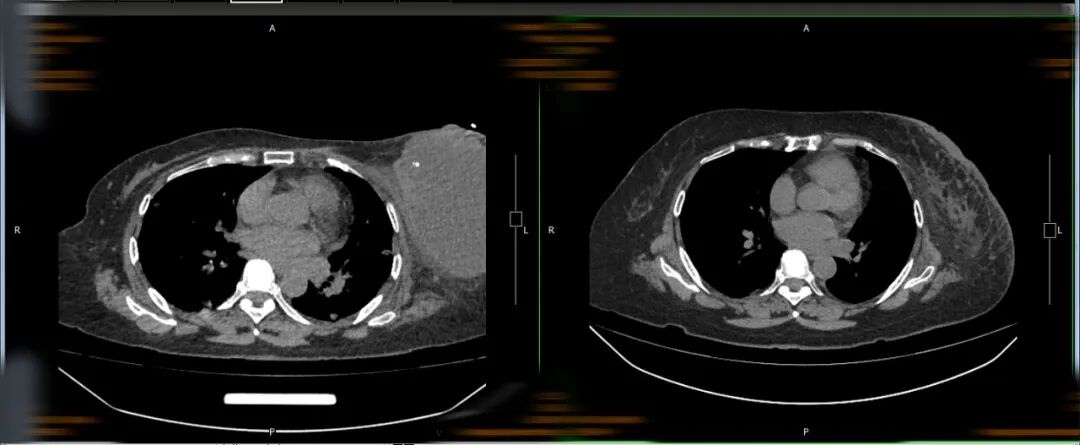

管床医生曾悦介绍,2022年7月4日,婆婆被确诊为乳腺癌 肺转移IV期。后来,她积极治疗,经历了化疗、免疫治疗,左侧乳腺肿瘤及肺部肿瘤较前明显缩小,病情得到了很好的控制。正当她认为自己的生活即将回到正轨时,命运又和她开了一个巨大的玩笑。她发现自己的右侧下肢“不太对劲”,走路使不上劲儿。于是,她在家属的陪同下来到医院检查。

入院时,婆婆右侧上下肢活动障碍并进行性加重,完善颅脑增强核磁,核磁示双侧额叶、左侧枕叶多发占位性病变,部分伴瘤周水肿,结合病史考虑转移瘤。

肿瘤科主任杨勇全面评估了王婆婆的病情,予全脑放疗联合脱水治疗。7次放疗结束后,婆婆右侧上下肢活动障碍较前明显缓解。所以出现了让工作人员余美华吃惊的一幕。